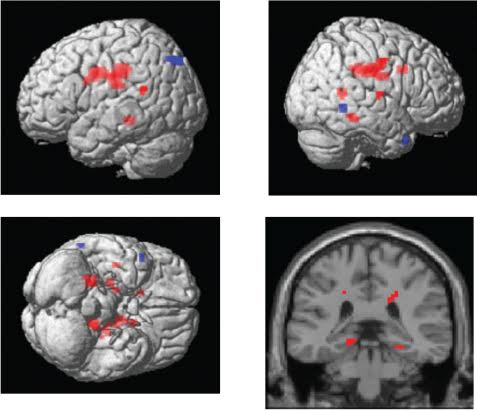

Les travaux, menés dans le cadre du vaste programme américain ABCD (Adolescent Brain Cognitive Development), se sont appuyés sur des données d’imagerie cérébrale et des évaluations psychologiques. Les chercheurs ont constaté que les adolescents ayant tendance à s’isoler présentaient des différences significatives dans plusieurs régions du cerveau. Leur cortex était légèrement plus mince dans des zones cruciales pour la perception sociale et émotionnelle, comme l’insula ou le gyrus temporal supérieur. À l’inverse, certaines structures internes, notamment l’amygdale et les ganglions de la base — connues pour réguler les émotions et la mémoire —, affichaient un volume plus important.

Ces différences ne sont pas anodines. Elles révèlent que la solitude, qu’elle soit choisie ou subie, influence la manière dont le cerveau se structure et communique. Les adolescents qui préfèrent la solitude semblent développer des circuits neuronaux plus cloisonnés, moins connectés aux réseaux de l’attention et de la cognition sociale. Ceux qui, au contraire, se replient sur eux-mêmes par détresse ou anxiété présentent une connectivité cérébrale plus faible dans certaines zones motrices et émotionnelles.